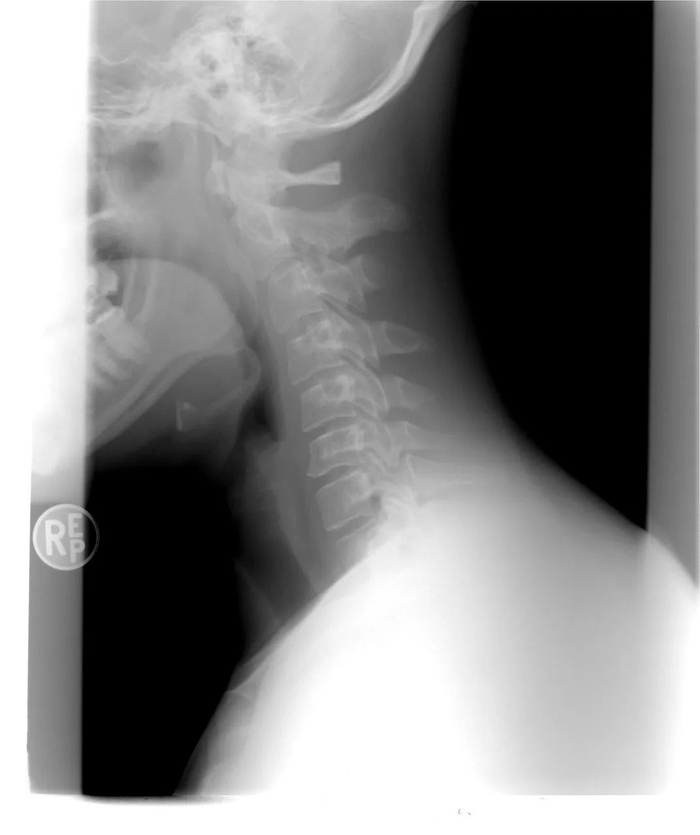

陈筠说,刚开始她经常头晕、犯困,有时候还会反胃,但并不知道自己是颈椎出了问题,直到被有经验的同事提醒她“去看看颈椎”。拿着医院拍出的X光片的她,正式被医生确诊了交感神经型颈椎病。那一年陈筠才23岁。